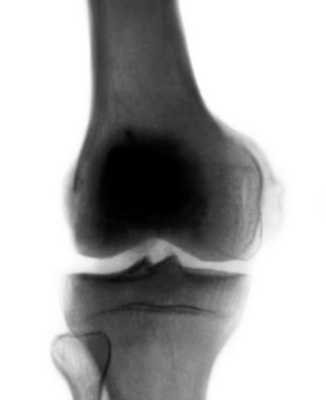

В раннем периоде после травмы, когда клиническая картина идентична ушибу или дисторсии коленного сустава, а также при сочетании с внутренними повреждениями его диагностика затруднена. Через 3—4 недели после травмы на рентгенограммах коленного сустава определяют оссификат (рис.), имеющий вид скобки, серпа или неправильную форму, который отделен от надмыщелка бедренной кости полоской просветления. При отрицательных рентгенологических данных, но при наличии пальпируемого оссификата необходимо произвести рентгеновские снимки с внутренней или наружной ротацией конечности на 20° для устранения наслоения оссификата на контур мыщелка бедра. Информацию о степени зрелости оссификата может дать радионуклидное исследование. Дифференциальный диагноз проводят с отрывным переломом медиального надмыщелка бедренной кости, который выявляется на рентгенограмме сразу после травмы. Кроме того, краевой дефект надмыщелка по форме и размерам соответствует оторванному фрагменту кости. Похожую рентгенологическую картину можно наблюдать при перестроенном процессе в надмыщелке тракционного генеза, возникающем в результате многократных форсированных напряжений большой приводящей мышцы бедра, например у футболистов. Однако постепенное развитие этого заболевания, более молодой возраст, связь с занятиями спортом помогают уточнить диагноз.

оссификация в области прикрепления большой приводящей мышцы бедра и медиальной коллатеральной связки коленного сустава к медиальному мыщелку бедра, а также по ходу связки">

Рентгенограмма коленного сустава (прямая проекция) при болезни Пеллегрини — Штиды: оссификация в области прикрепления большой приводящей мышцы бедра и медиальной коллатеральной связки коленного сустава к медиальному мыщелку бедра, а также по ходу связки.

Болезнь Пеллегрини — Штида проявляется обызвествлением мягких тканей в области внутреннего мыщелка бедра, что рентгенологически наблюдается в виде различных размеров теней. Клинически картина заболевания довольно неясная. После травмы появляются боли, чаще с внутренней стороны сустава. Сгибание ограничено. Пальпацией определяются болевые точки в области внутренного надмыщелка бедра выше уровня суставной щели. На фасной рентгенограмме коленного сустава обнаруживается костная тень в виде небольшого полулуния или скобки, расположенная на типичном месте у верхнего края внутреннего мыщелка бедра, параллельно его корковому слою, отделенная от него светлым промежутком. Этот костный участок является не отломком поверхностной пластинки коркового слоя, а обызвествлением или даже окостенением в сухожилии большой приводящей мышцы бедра. Киста мениска коленного сустава может располагаться как во внутреннем, так и наружном мениске. Последнее наблюдается гораздо чаще. Характерным является болезненность по соответствующей суставной щели, усиливающаяся при движении и нагрузке. Здесь же иногда видна припухлость, размер которой может варьировать.

В раннем периоде после травмы, когда клиническая картина идентична ушибу или дисторсии коленного сустава, а также при сочетании с внутренними повреждениями его диагностика затруднена. Через 3-4 недели после травмы на рентгенограммах коленного сустава определяют оссификат (рис.), имеющий вид скобки, серпа или неправильную форму, который отделен от надмыщелка бедренной кости полоской просветления. При отрицательных рентгенологических данных, но при наличии пальпируемого оссификата необходимо произвести рентгеновские снимки с внутренней или наружной ротацией конечности на 20° для устранения наслоения оссификата на контур мыщелка бедра. Информацию о степени зрелости оссификата может дать радионуклидное исследование. Дифференциальный диагноз проводят с отрывным переломом медиального надмыщелка бедренной кости, который выявляется на рентгенограмме сразу после травмы. Кроме того, краевой дефект надмыщелка по форме и размерам соответствует оторванному фрагменту кости. Похожую рентгенологическую картину можно наблюдать при перестроенном процессе в надмыщелке тракционного генеза, возникающем в результате многократных форсированных напряжений большой приводящей мышцы бедра, например у футболистов. Однако постепенное развитие этого заболевания, более молодой возраст, связь с занятиями спортом помогают уточнить диагноз.